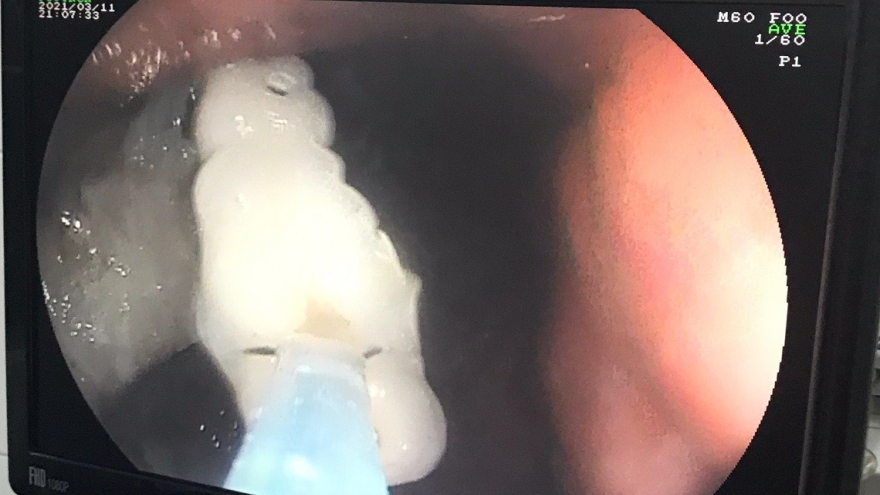

Can thiệp lấy 4 răng giả "lạc" trong dạ dày của bệnh nhân 61 tuổi

VOV.VN - Các bác sĩ Khoa Nội soi của Bệnh viện Đa khoa Trung ương Cần Thơ vừa can thiệp thành công một trường hợp có 4 chiếc răng giả trong dạ dày với thời gian 3 phút.